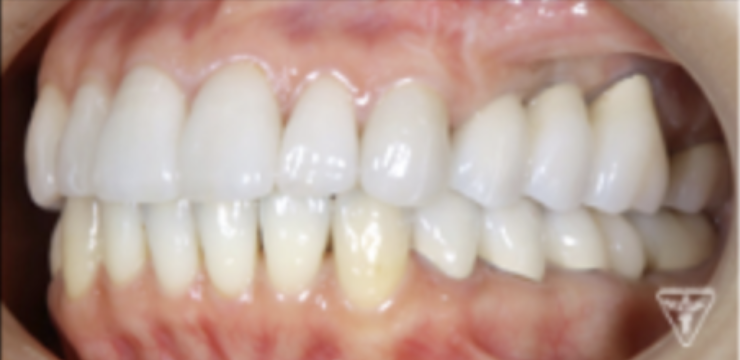

咬合調整

粉砕効率の高い小さな点による均衝接触をつくります。

咬合様式は、ミューチャリープロテクトオクルージョンを付与しました。